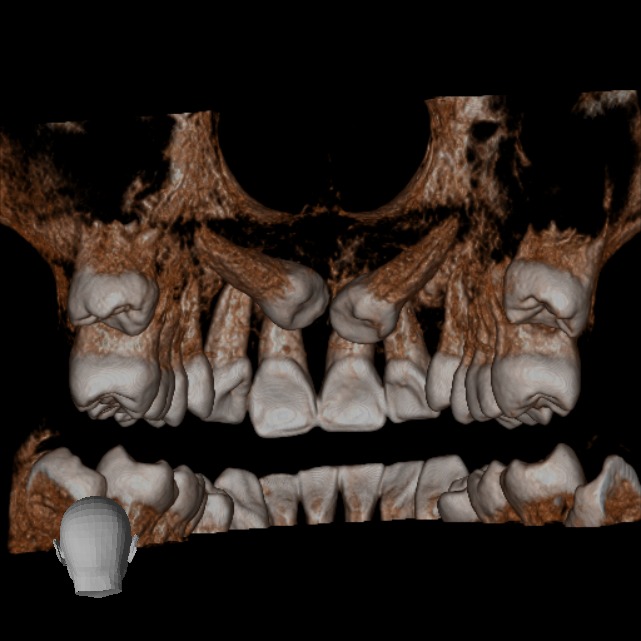

Tomografía CBCT

En nuestra clínica en Bogotá contamos con equipos de tomografía CBCT de última generación, que garantizan la más alta calidad en diagnóstico dental y permiten a tu odontólogo planificar cada detalle de tu tratamiento con máxima precisión.

• Rápido – Cómodo – Eficaz: Las imágenes obtenidas con nuestros equipos son altamente detalladas, mostrando los tejidos duros sin perder calidad.

Podemos analizar la posición y orientación de estructuras críticas como los nervios, las raíces dentales, los senos paranasales y la nariz, lo que ayuda a lograr un diagnóstico lo más preciso posible. Con nuestra tecnología de imagen avanzada, tu odontólogo podrá monitorear la estabilidad a largo plazo de tus restauraciones dentales, de esta forma se podrá obtener el resultado estético que deseas con tu tratamiento.